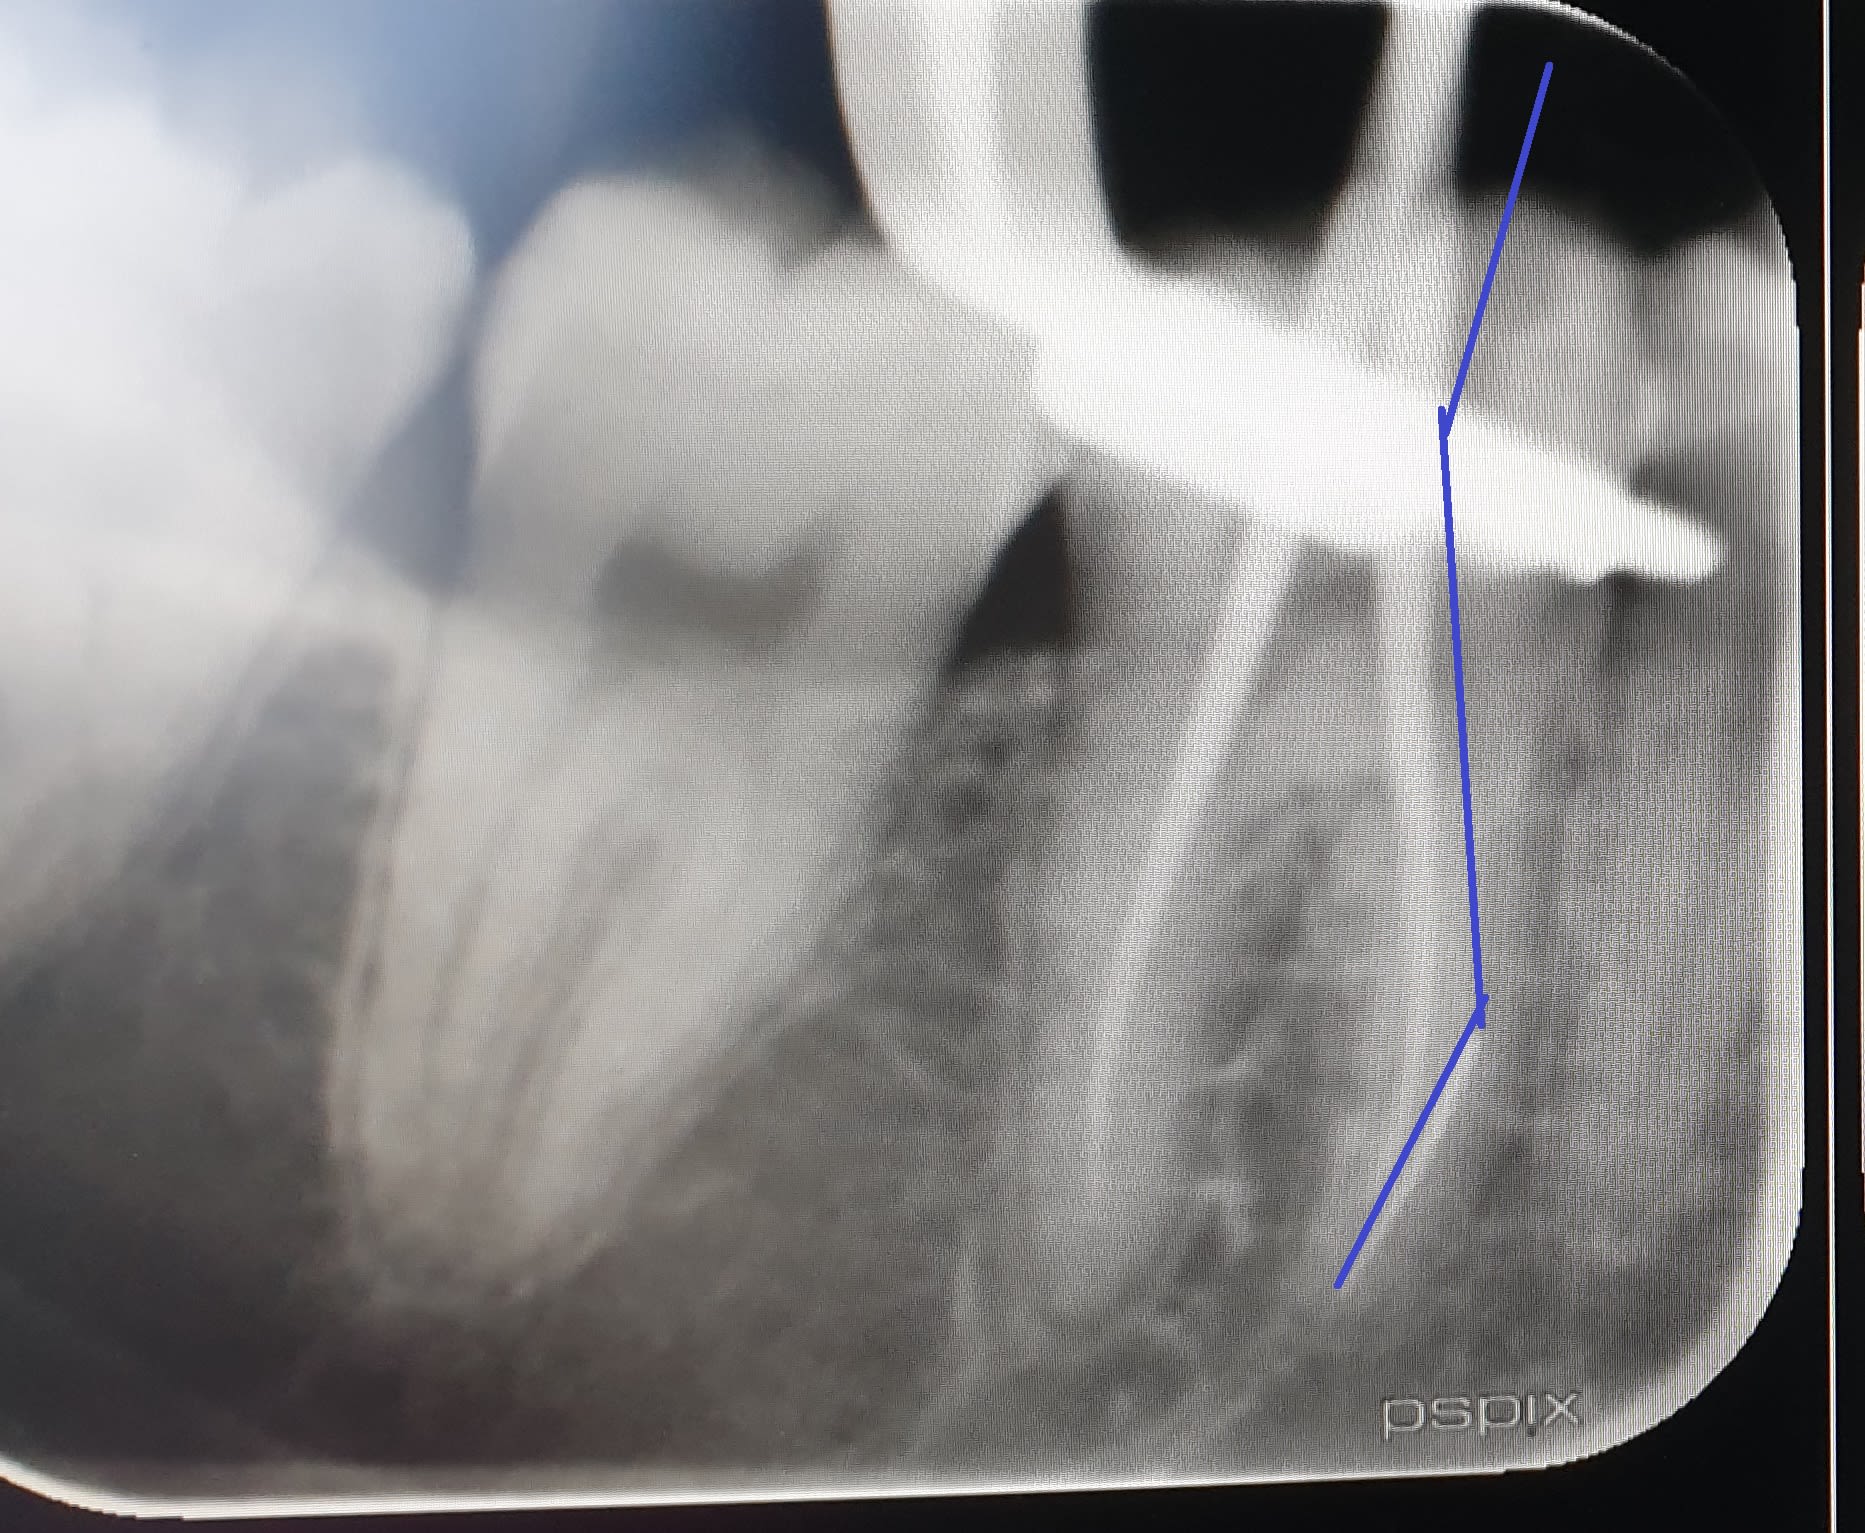

C'est ça, en fait l'ouverture de chambre réduite impliquait d'anguler le contre angle en distal, pour rester dans l'axe de l'entrée canalaire.

Le crampon, déjeté en direction mésiale, a probablement repoussé la tête de contre angle ----> double courbure ----> clac

Ca aurait probablement pu être évité en passant un forêt un peu large dans le tiers coronaire, ou en shootant la paroi mésiale (saine) de la dent, ou en dégageant la digue plus distale.

Ce qui n'enlève rien au fait que pour moi, et jusqu'à preuve du contraire, la dent est conservable en l'état, avec un compo simple dans la chambre, et en pensant à diminuer les pentes cuspidiennes pour éviter la fracture du pan lingual.